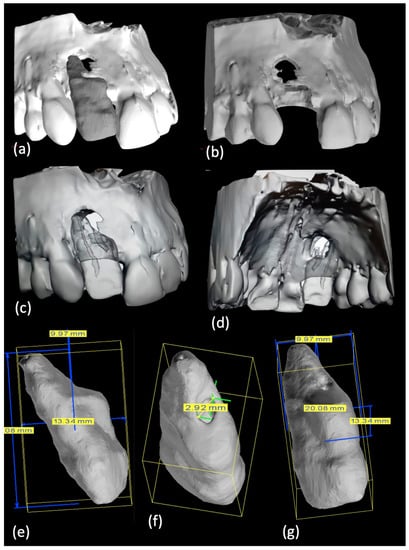

Print and Try technique and treatment planning: The CBCT file was transformed in an STL one. On the STL file the bone structure was previewed with and without the tooth (Figure 2a–d–Movie 2) and tooth dimensions, including the invagination size, were measured (Figure 2e–g).

Figure 2.

(a–d) An STL of bone structure with and without element 1.2 was produced and (e–g) dimensions of element 1.2 were achieved.

Afterwards alveolar bone with and without the tooth was printed using the 3DSlicer software and a Formlabs printer (Figure 3a,b); a specific tooth model was obtained through a Meshmixer software and a Stratasys printer (Figure 3c).

Figure 3.

(a,b) Customized bone and (c) tooth 3D-models were printed. (d) Main root canal therapy and invagination retrograde filling were performed on 3D-tooth model.

A clear material was chosen for the single tooth model (VeroClear, Stratasys, Eden Prairie, MI, USA), thus enabling visualization of both the root canal system and the instruments used at the different negotiation stages. Working on the 3D-printed models it was possible to determine the best treatment option which would have comprise of a primary orthograde endodontic treatment for the main canal, immediately followed by a surgical approach to achieve an adequate sealing of the invagination (Figure 3d). On the transparent tooth model, an occlusal distal conservative access cavity was centered on the main canal and then flexible rotary instruments were tried in to negotiate the canal lumen. A flexible irrigation plastic needle was confirmed to reach within 1 to 2 mm from the working length, even in the presence of a significant curvature between the middle and last third of the canal; also, the obturation stage was rehearsed and it was confirmed that a 3D-filling with warm gutta-percha was achievable. Finally, a complete infill of the invagination was practiced in a mock surgery with a putty bioceramic material. All these steps are reported in Movie 3.

Print and Try technique and treatment planning: From the CBCT dicom file, an STL file was converted to generate a whole image of the teeth and supporting bone in three planes, thus allowing a better three-dimensional understanding of the structure involved (Figure 7a–l); subsequently a 3D plastic model was obtained with a Stratasys printer, using a clear material (Figure 7m) (Movie 8).

Figure 7.

(a–l) CBCT data were uploaded to an STL software and (m) a transparent plastic model was three-dimensionally printed.

The 3D model, inclusive of its hollow root canal system, was used to carry out a mock orthograde endodontic therapy, in particular the best access cavity was determined to localize the position of each orifice in anticipation of the actual treatment. The canals were negotiated with a preliminary rotary scout instrument: the clear roots allowed to understand where the instruments were likely to stop or create an inappropriate path. Rotary files with reduced taper were then used and it was possible to reach the full working length and gauge the apical foramen. An irrigation plastic needle could reach within 1 to 2 mm from the working length. Finally, a single cone filling technique, combined with a bioceramic sealer, was tried in the model tooth.